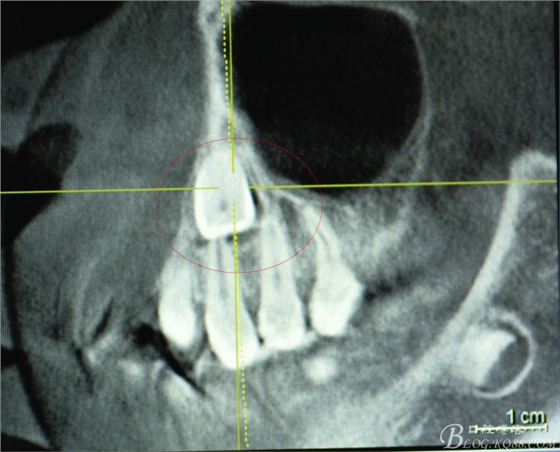

圖1.術(shù)前患者在當(dāng)?shù)嘏娜捌?,發(fā)現(xiàn)23位于24根尖部,經(jīng)正畸科會(huì)診,建議拔除23,遂拍cbct檢查:23牙冠騙近唇側(cè)。

圖2.冠向切面、23位于24根尖區(qū)、24牙根未見吸收

圖3.矢狀面檢查:23的唇面接近唇側(cè)骨壁、從而提示切口應(yīng)做在唇側(cè)。